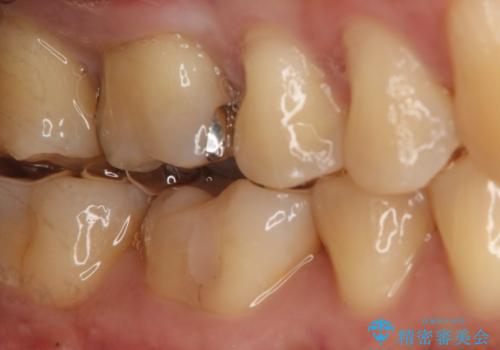

- 右上6番の銀歯をセラミックに変えたいと希望された患者様です。

切削量、形態を考慮し、セラミックインレーでの治療を計画しました。

銀歯と虫歯を除去した上でCRで裏層し形態を整えて印象を行っています。